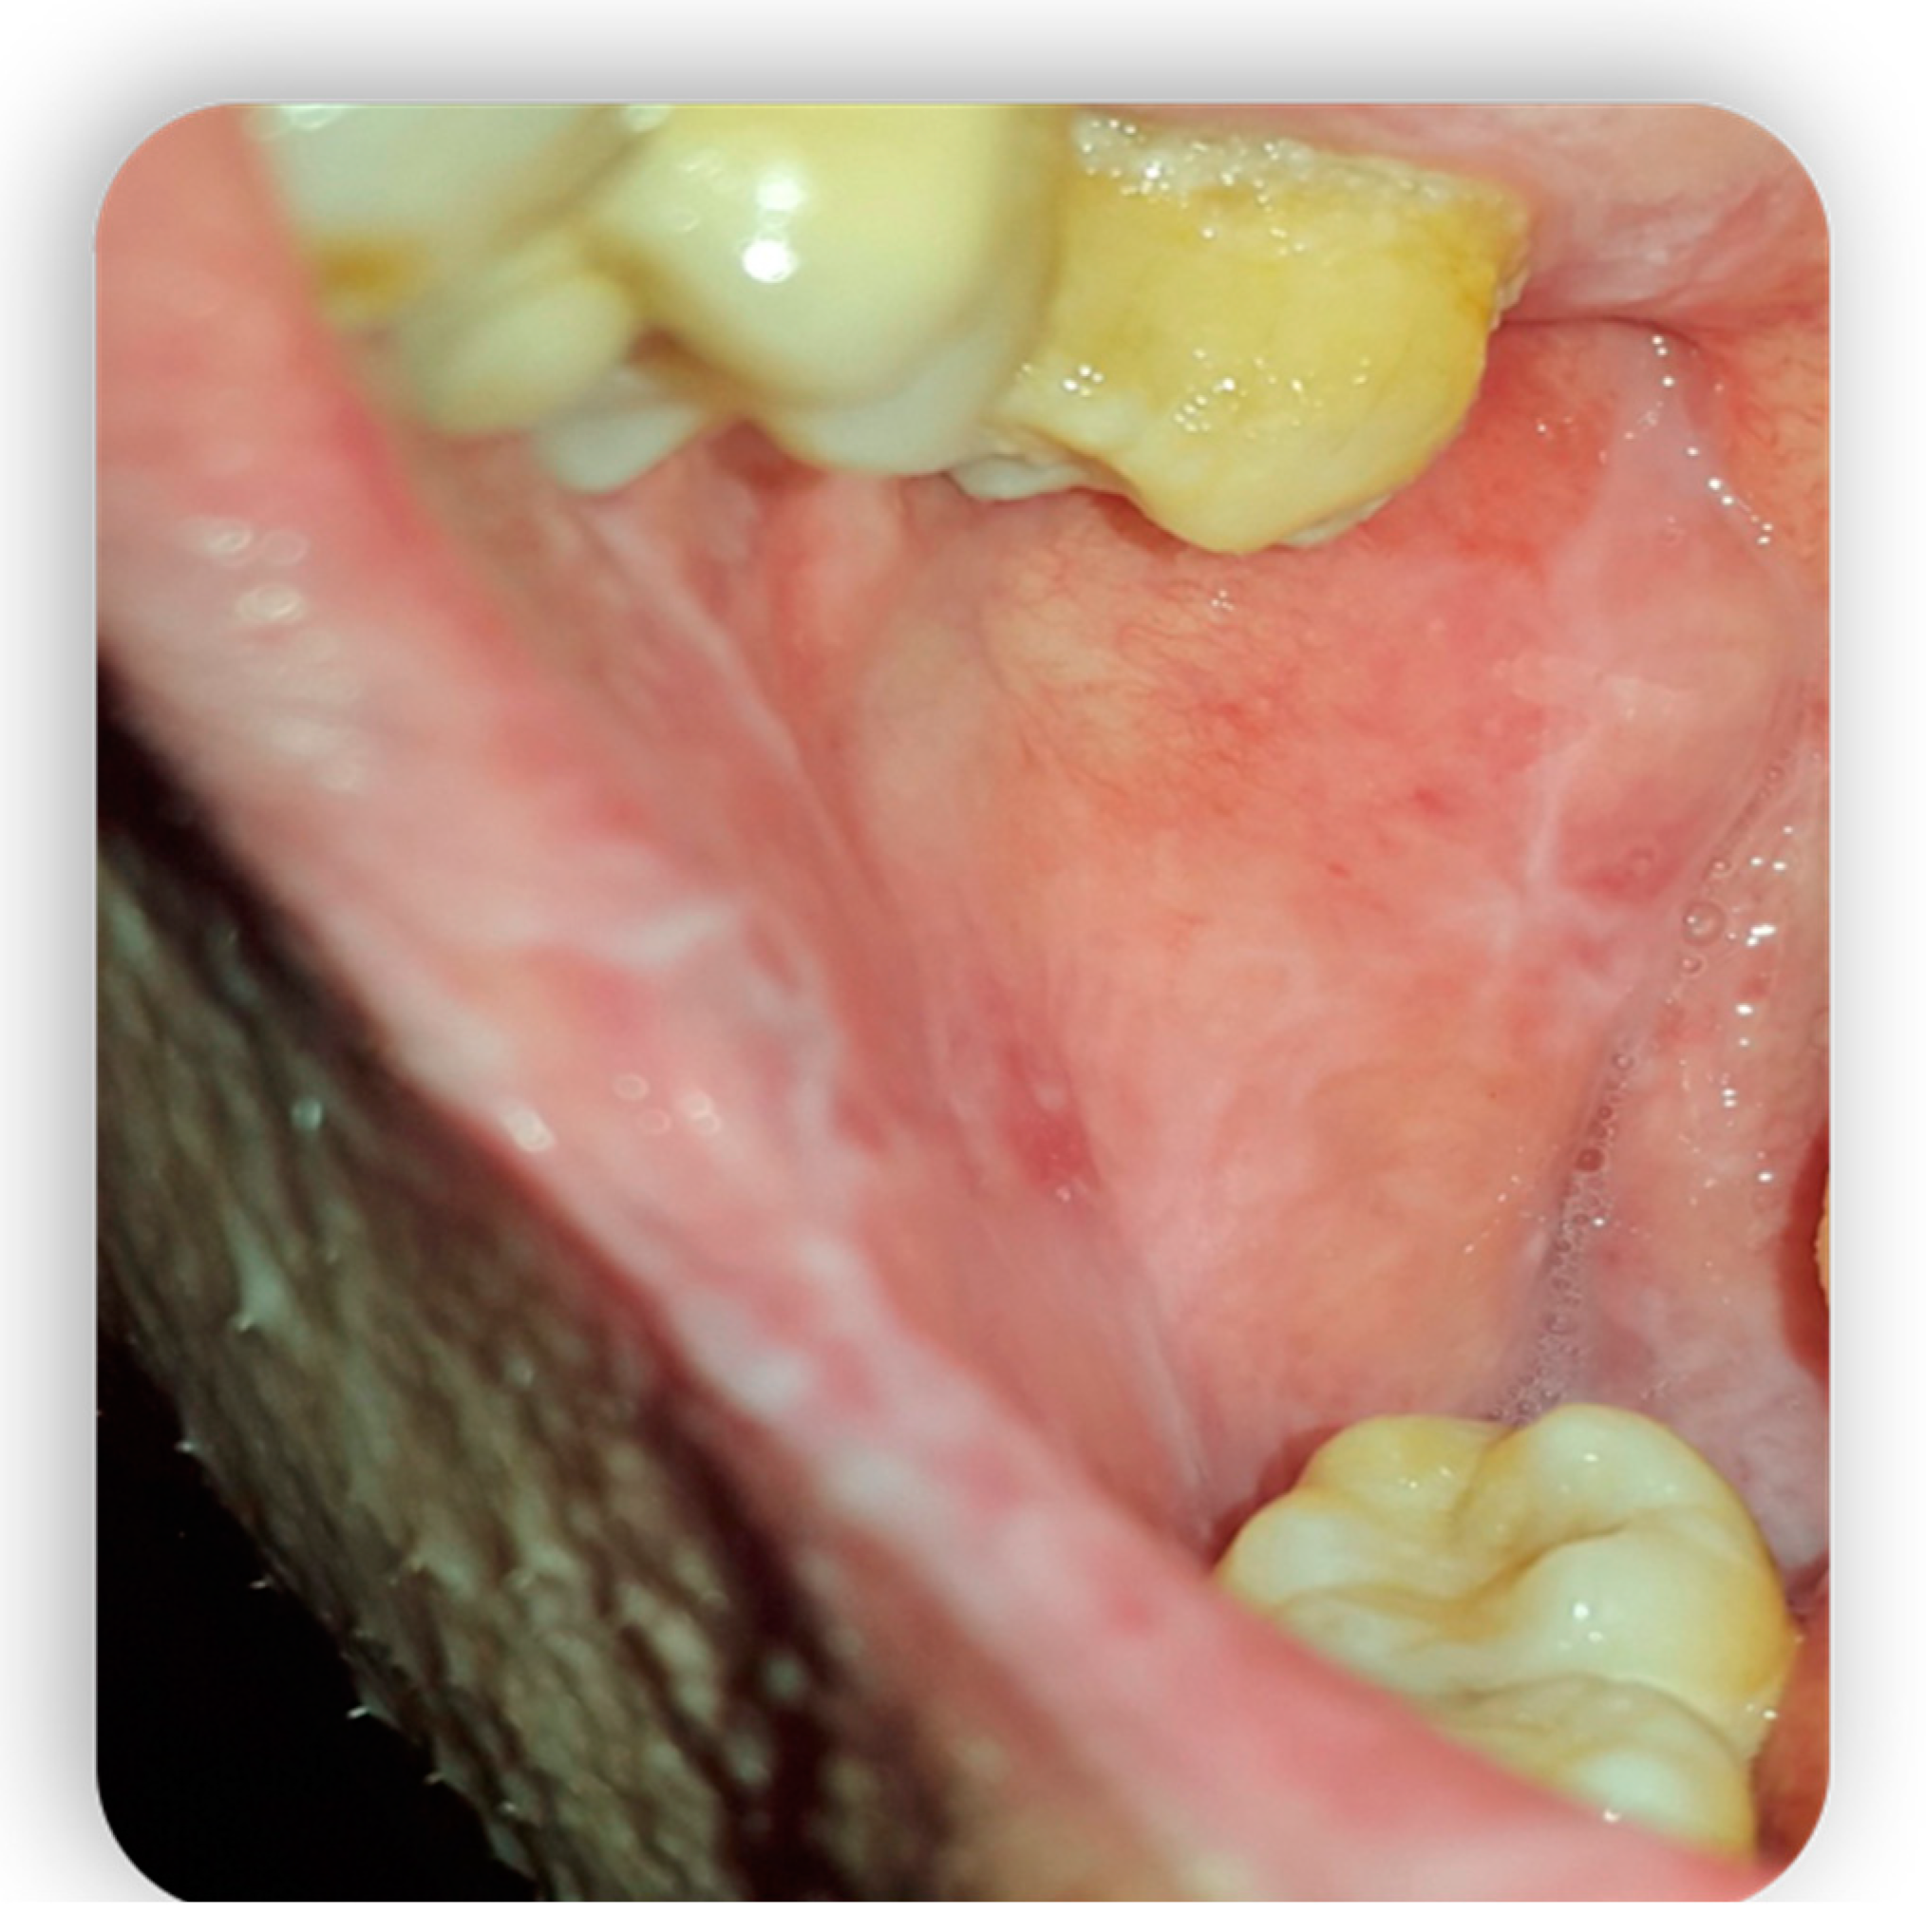

1.4.2. Oral aGvHD Manifestation

The oral manifestations in acute GvHD are very infrequent and therefore there is no well-defined characterization in the literature. In fact, some authors such as Zeiser [7] in their 2004 and 2006 studies, respectively, do not consider acute oral GvHD to be a distinct clinical entity since the lesions are indistinguishable from those of conditioning. However, Ion’s work in 2014 showed lesions such as generalized erythema and pseudomembranous ulcerations [31], mucosal atrophy, and hyperkeratotic striae (lesions similar to the Wickham striae of lichen planus) [32]. Acute GvHD oral lesions are considered those that occur 3 or 4 weeks after transplantation. The sites most affected by oral aGvHD are the non-keratinized oral mucosa, the tongue (especially the ventrolateral and dorsal portion), the labial mucosa, and the hard and soft palate [30]. Gingival involvement is less frequent. In severe cases, patients may also present with xerostomia and salivary gland hypofunction. Histologically, the epithelium of the mucosa shows variations in thickness and has variable alterations ranging from dyskeratosis to reactive atypia. The signs of acute or chronic inflammation of the lamina propria are practically always present (Figure 3 and Figure 4) [33].

Figure 3.

Oral mucositis manifestations from Gvhd.

Figure 4.